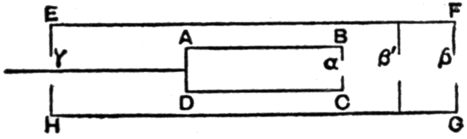

Fig. 1.—Head.

Fig. 2.—Broken Arm, Overlapping.

(Due to defective setting.)

Fig. 3.—Ribs.

Fig. 4.—Knee, Knickerbocker Buttons, Bullet in Femur.